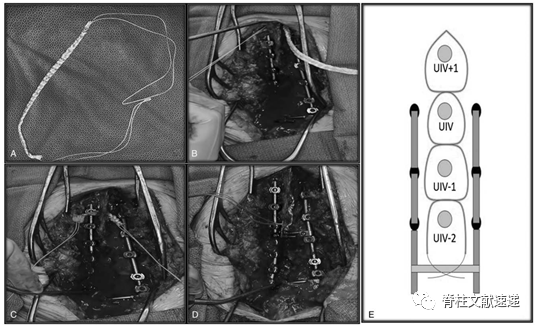

六、椎板下绑带的应用